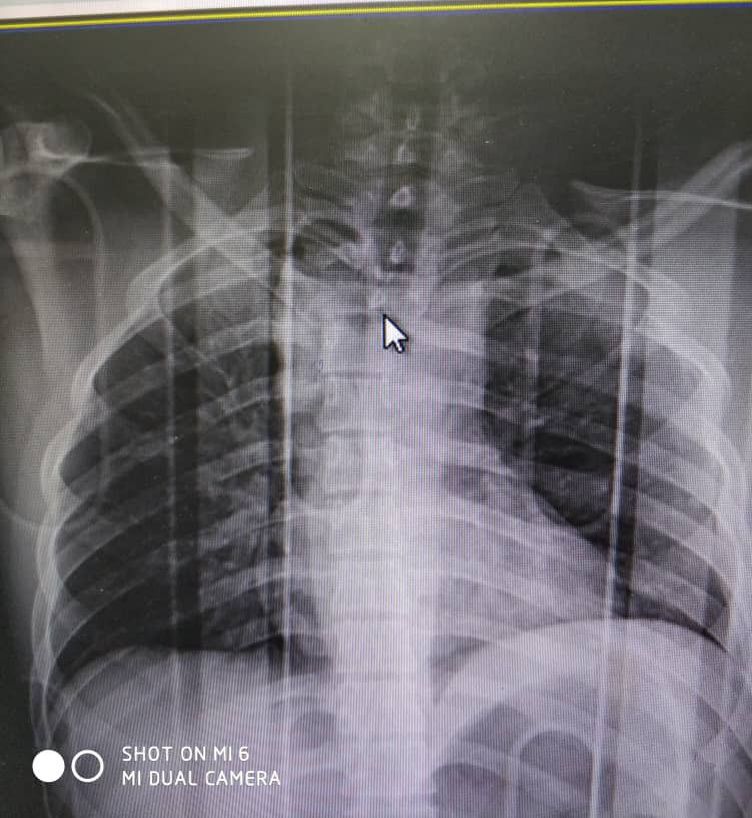

Accident car

Car accident Thorassic trauma ;car

Neurosurgery

Emergencyroom